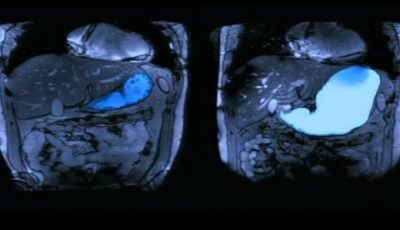

S02E02 | Scotland's Superhospital

S02E02 | Scotland's Superhospital

Staff are excited to be part of a new clinical trial which could revolutionise kidney dialysis.